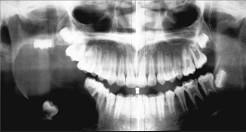

男,18岁,右颌下区反复肿胀半年,2天前再次发作,病程进展快,出现张口受限。X线片示右下颌角区沿颌骨长轴有单囊阴影,包绕右下颌第三磨牙牙冠。该病人最可能的诊断是 ( )

A右下颌骨中央性癌

B右下颌骨骨髓炎

C右下颌造釉细胞瘤

D右下颌角化囊肿继发感染

E右下颌骨含牙囊肿